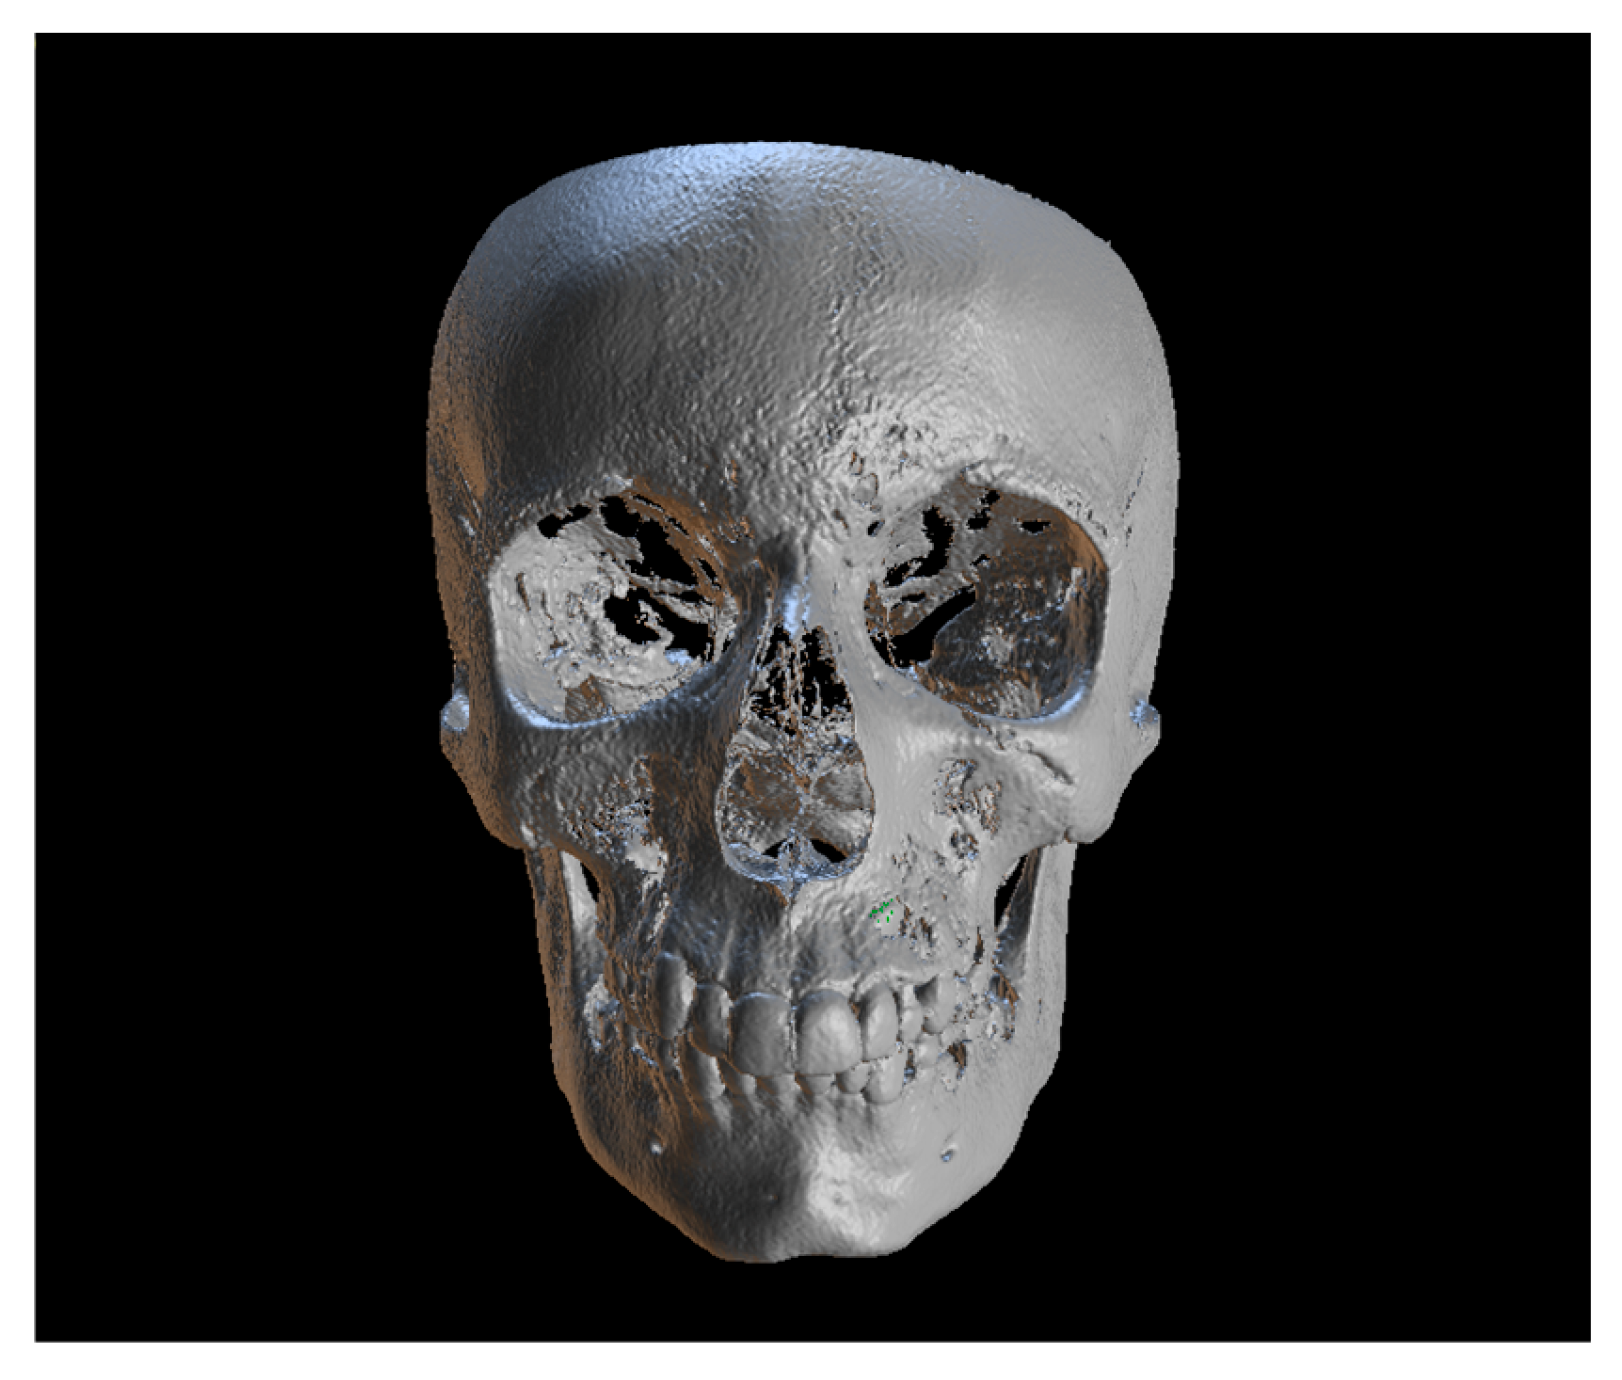

Since the IC is not visible in the initial STL, it was necessary to know its three-dimensional location. As performed in the other method, the initial CBCT scan (Figure 2) was opened in the program, and all teeth were segmented. Although Figure 2 shows the skull model, only the teeth segmentation is necessary for this method. A small cut was made to allow visualization of the IC (Figure 3).

Figure 2.

Initial CBCT scan.

A 13-year-old male patient presented with Class II Division 2 malocclusion, a bilateral Class II sagittal relationship, and retroclined incisors. Cone-beam computed tomography revealed a palatally impacted maxillary left canine (tooth 23), with its cusp located palatally to the apical half of the left lateral incisor. The root exhibited significant apical curvature, extending toward the floor of the maxillary sinus (Figure 12 and Figure 13), making spontaneous eruption unlikely.

Figure 13.

Impacted canine 23 with its cusp palatally positioned to the apical half of the left lateral incisor, with the root significantly curved and inserted into the maxillary sinus.